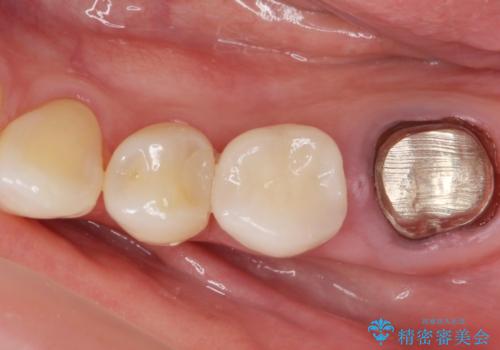

- 銀歯のやりかえ希望の患者様です。

症状もなく、レントゲンでも根尖病巣が見られないため

患者様と話し合った結果、中の土台は外さず、被せ物のみのやりかえとなりました。